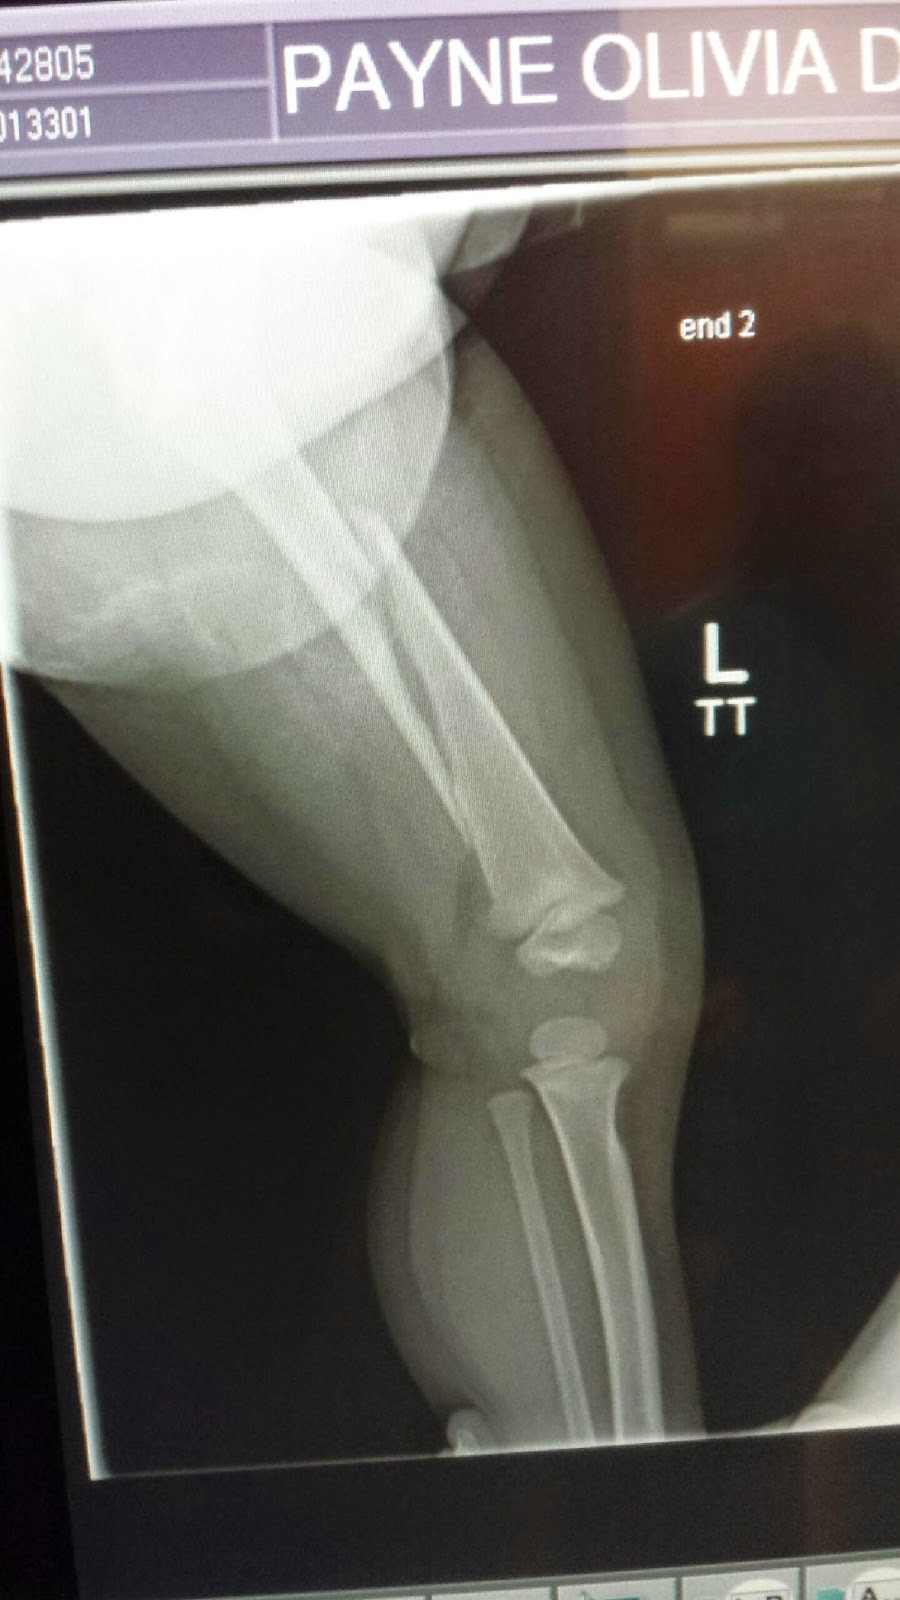

Femoral shaft fracture Open femoral fracture bone defect treated with

Broken Femur Xray Broken Femur Cast Goal is to have distal fragment match the position of. learn about the symptoms, causes, types, and treatments of a broken femur, a serious injury that may require. Breaking your femur is very painful and makes your leg look bent or floppy. You can't walk on it, so you'll need an ambulance. a broken femur can be an.. Broken Femur Cast.